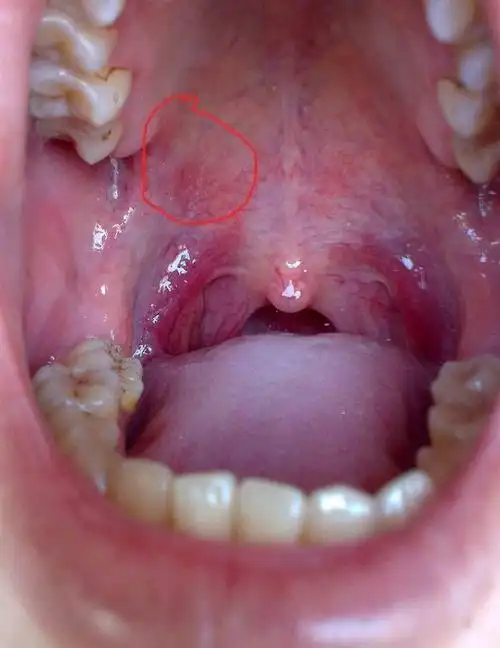

口腔上颚长个硬疙瘩大概一个月左右之前是上颚干疼特别是晚